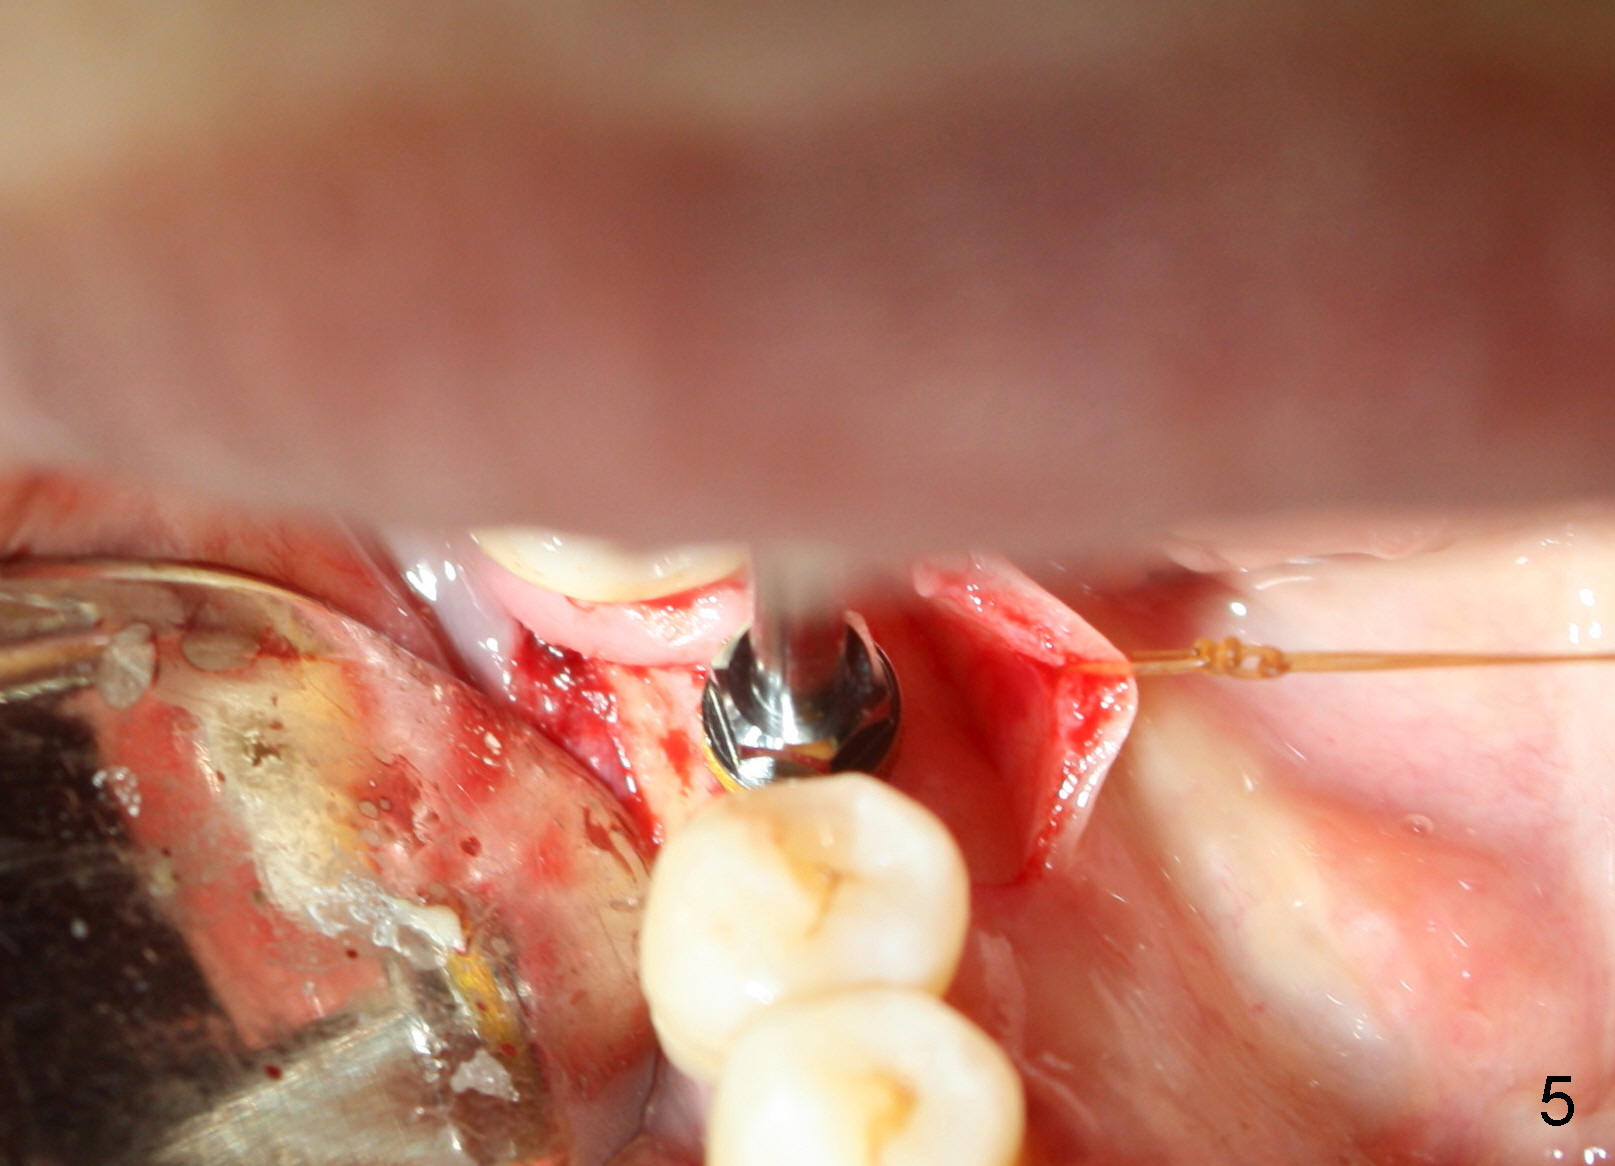

Due to unavailability of bone-level implant, a tissue-level implant is to be placed as a backup (Fig.1: 4.5x17 mm). Osteotomy is initiated with 1.5 mm pilot drill at depth of ~ 10 mm; the trajectory appears to be as good as expected (Fig.2). Osteotomy is gradually increased to 4.5x17 mm, followed by insertion of 4.5x17 mm tap (Fig.3,4). The ostetomy appears to be deviated lingual (Fig.5). When the tap is removed, the buccal plate appears to be thin (Fig.6). A tapered implant is placed (Fig.7).